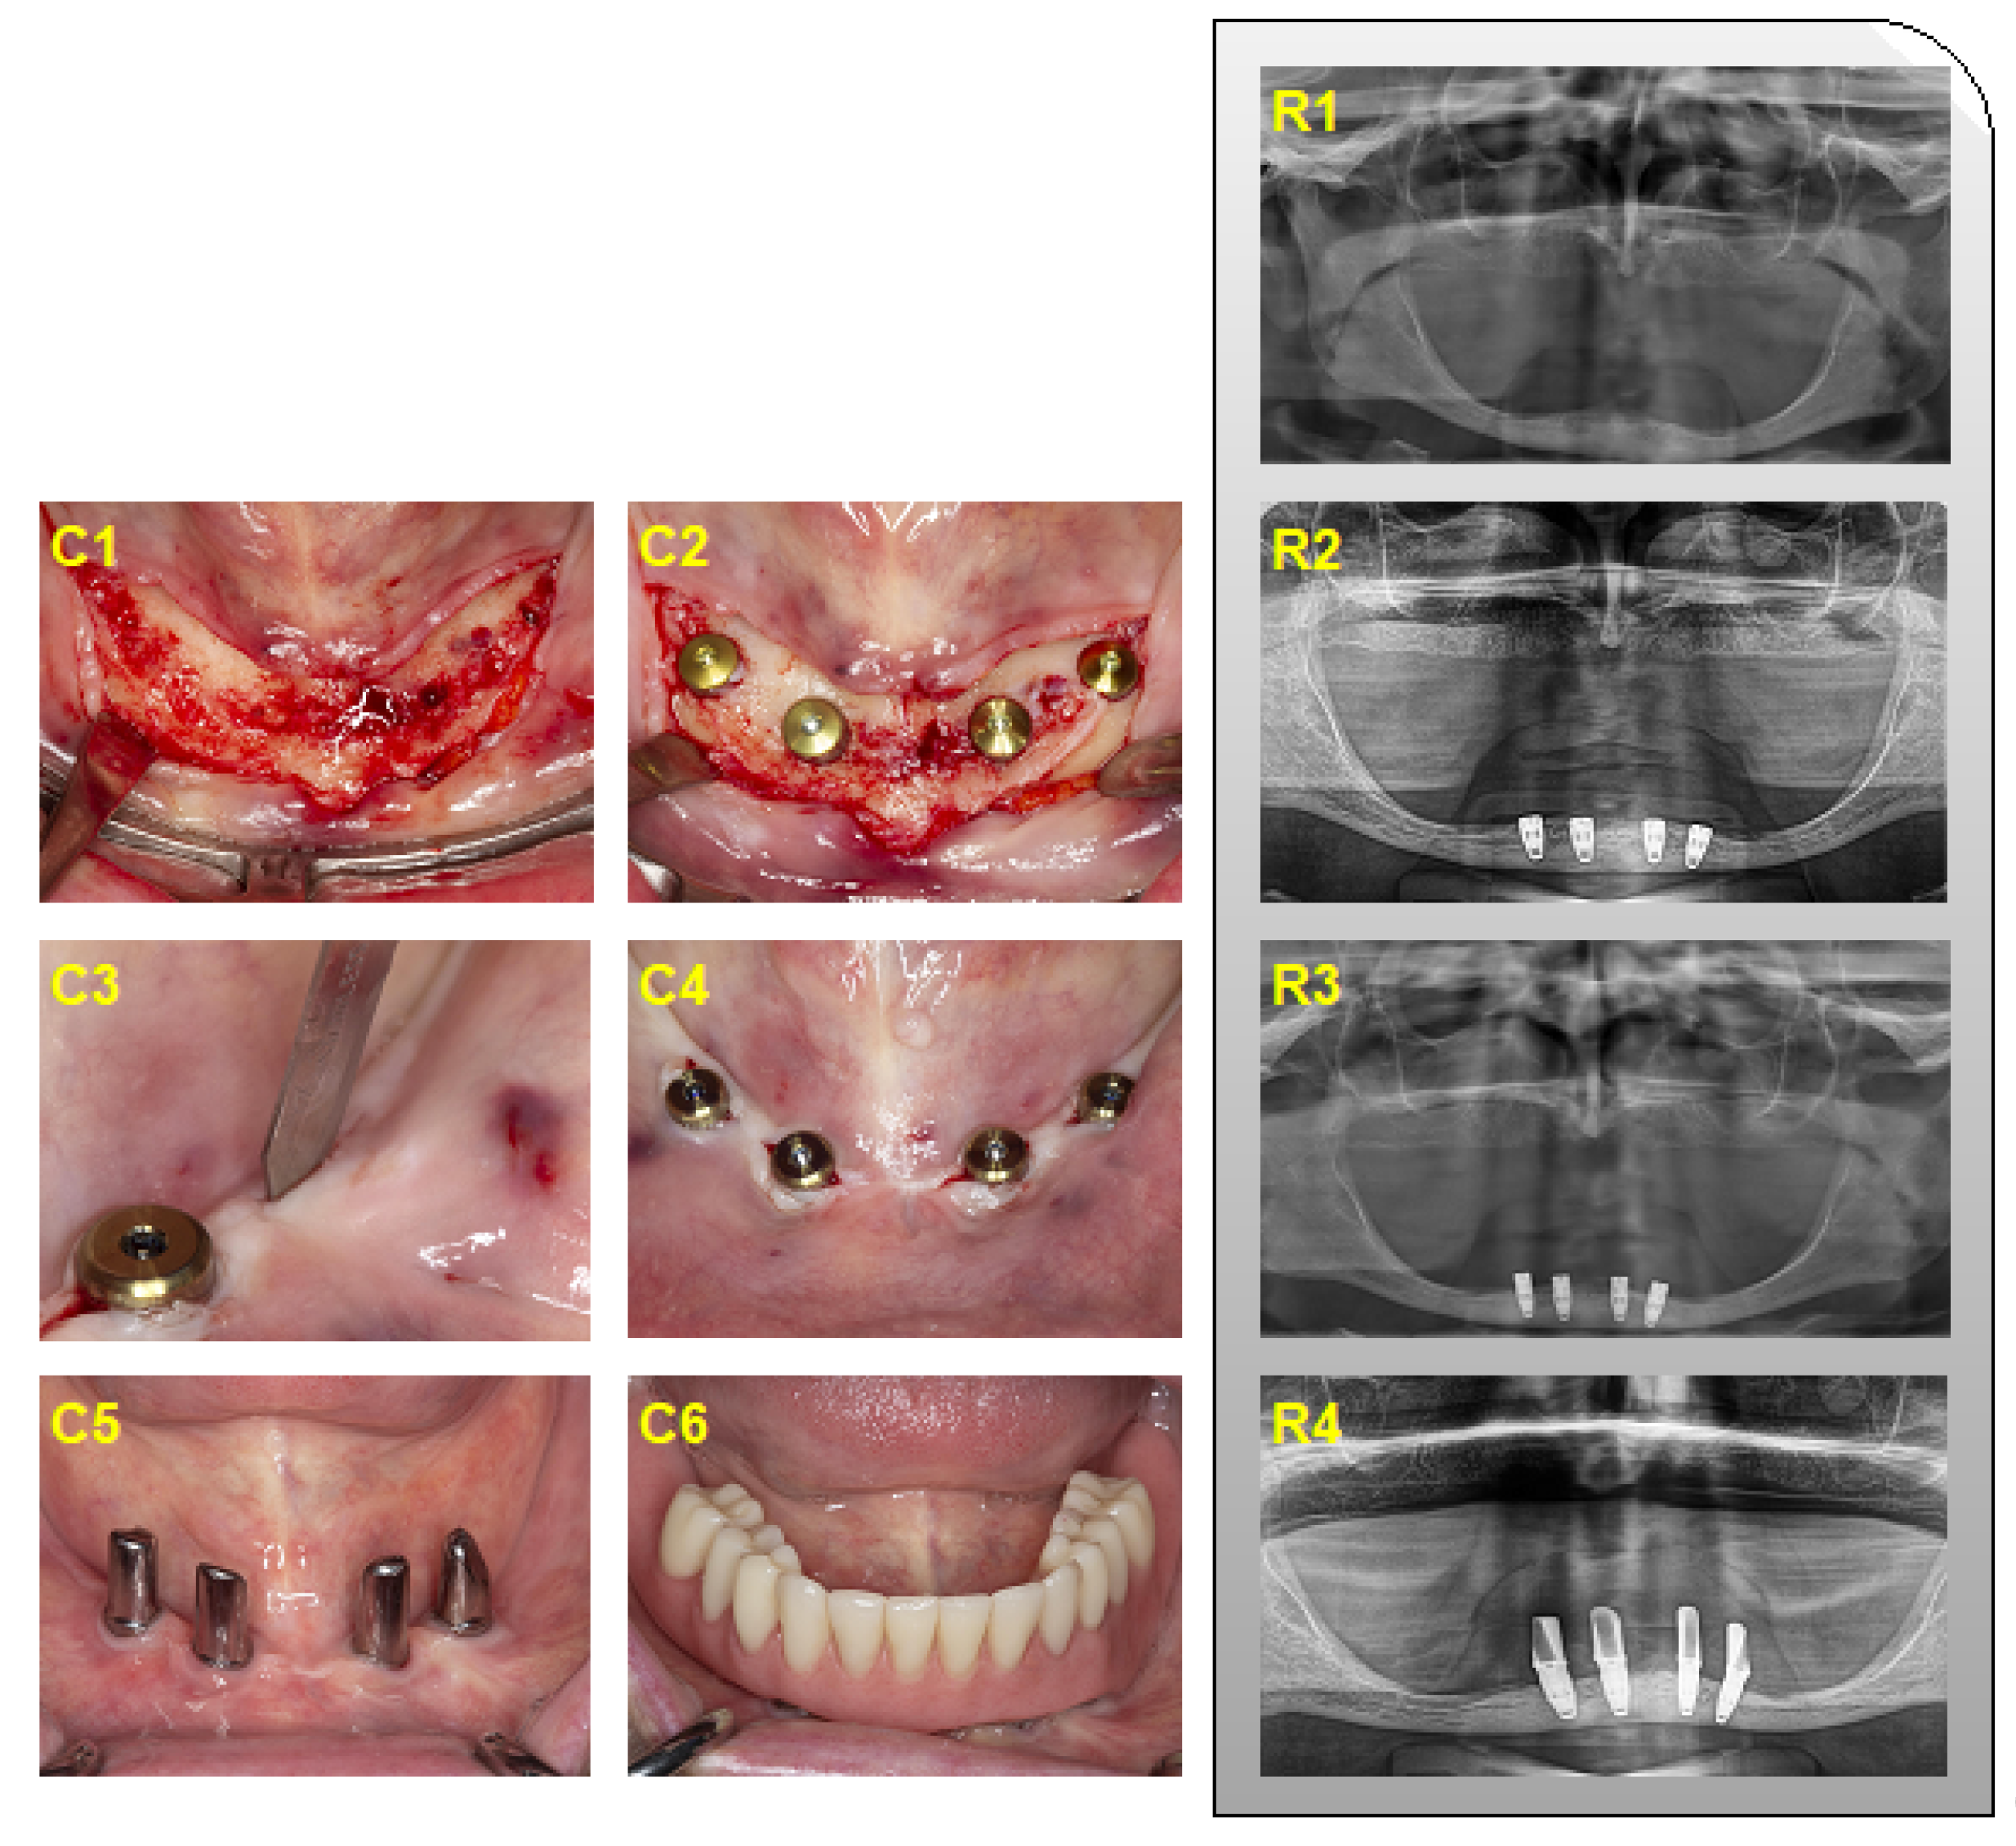

2.2. Clinical Treatment